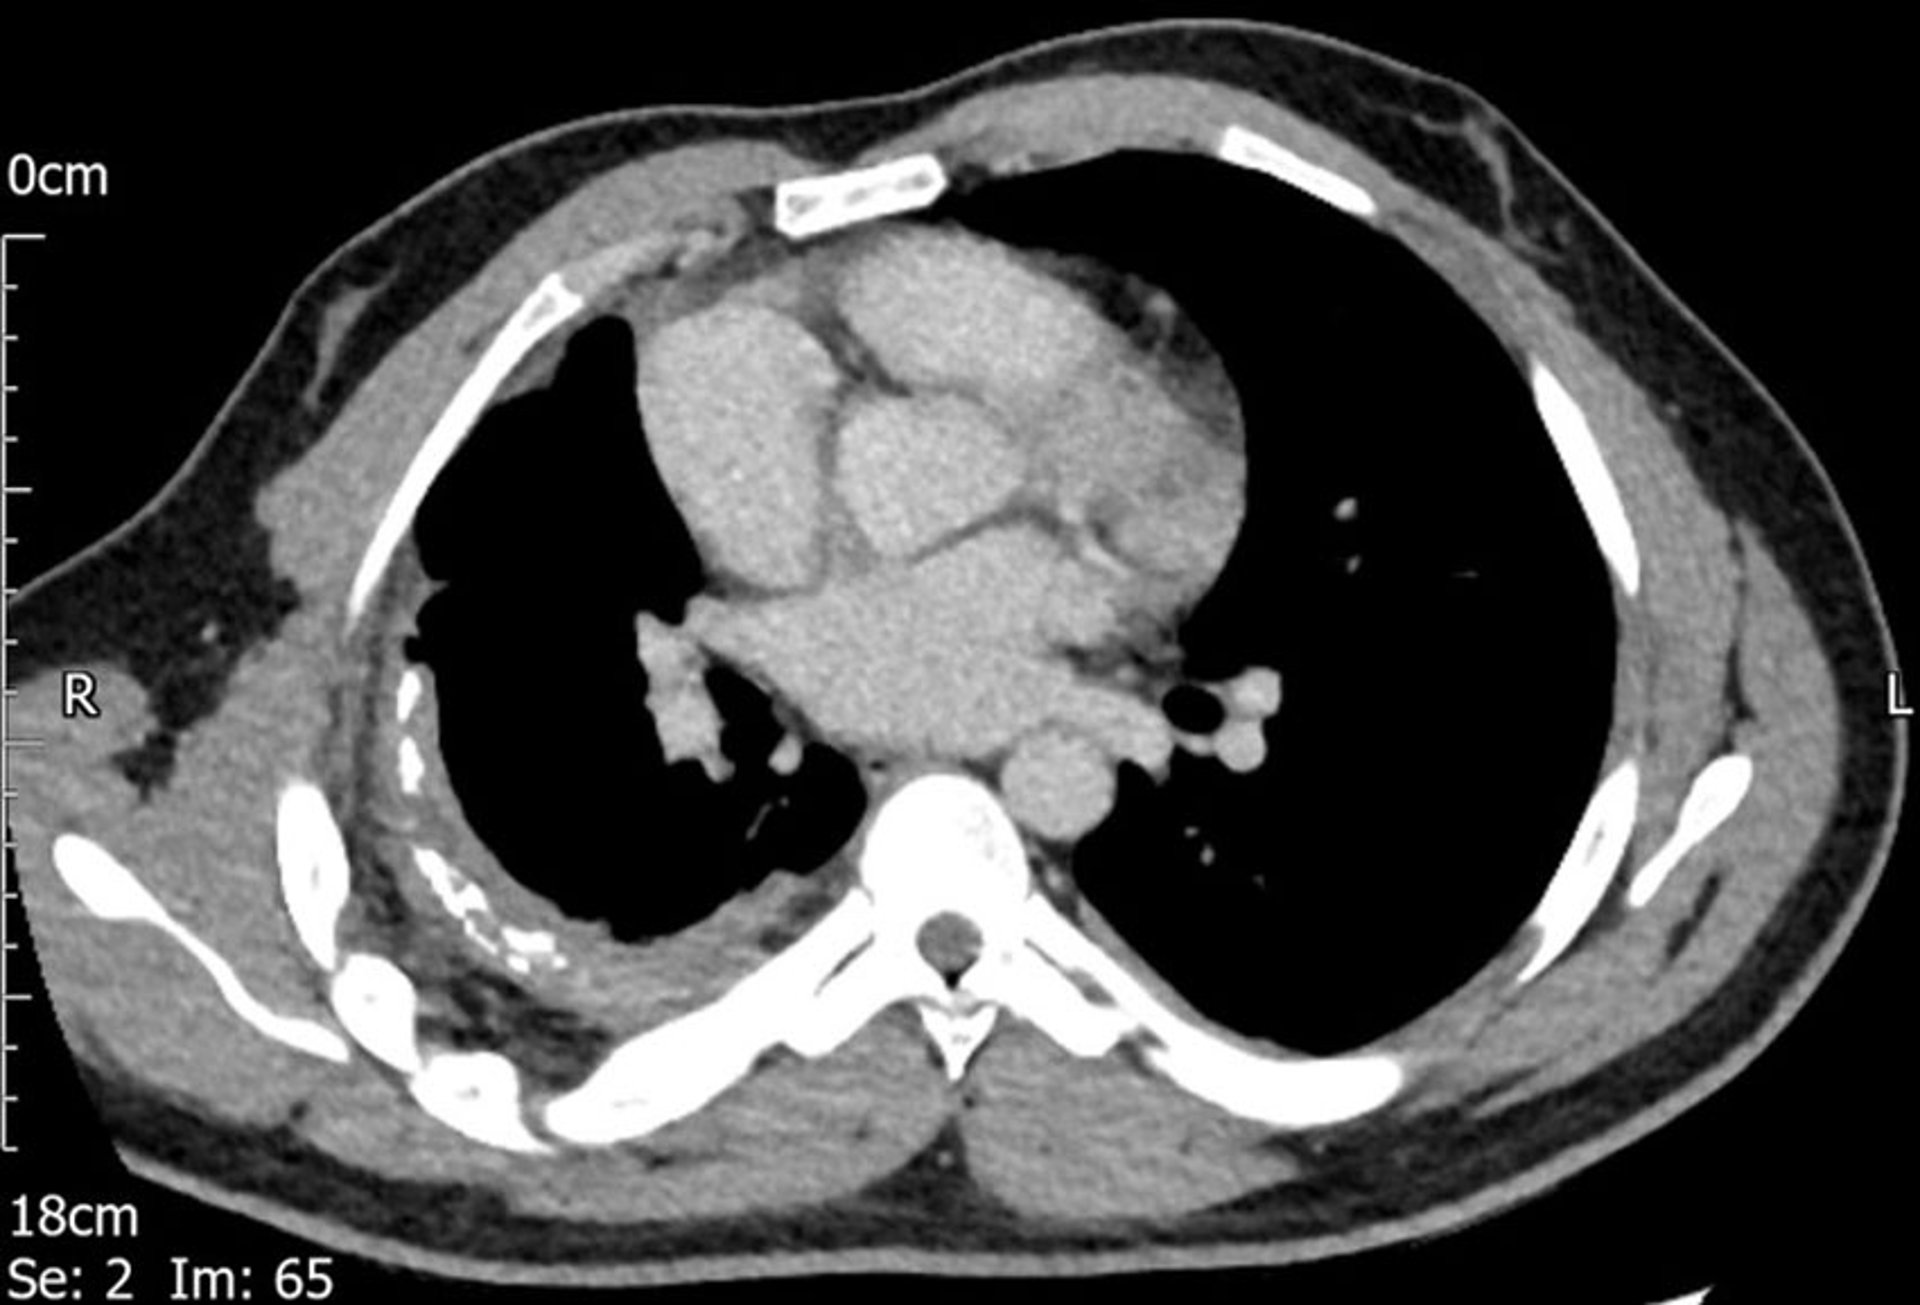

CT扫描显示右侧胸膜增厚。

Image courtesy of Najib M.Rahman, BMBCh MA (oxon) DPhil.

胸膜纤维化和钙化